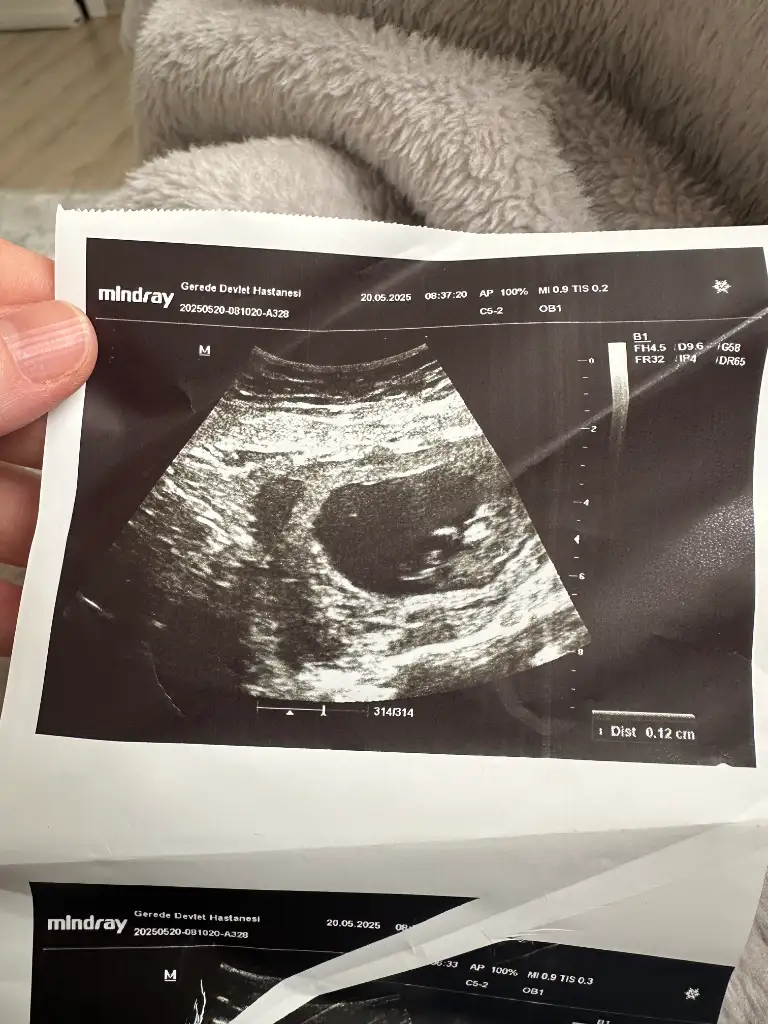

Ultrason görüntüsüne dayanarak gebeliğin yaklaşık 11. haftasında olduğunu görüyorum (aşağıda CRL ve GA bilgisi var). Bu haftalarda bebek henüz cinsiyetini ultrasonla güvenilir şekilde belli edecek kadar gelişmemiştir. Cinsiyet tahmini genellikle 13. haftadan itibaren daha net yapılabilir, ancak en doğru sonuçlar 16. haftadan sonra elde edilir.

• Bu görüntüde cinsiyet tahmini yapmak şu an için mümkün değil.

• En doğru tahmin için birkaç hafta sonra tekrar ultrason yaptırmanız önerilir.

Evet canım tam 11 haftalık onu doğru bilmiş